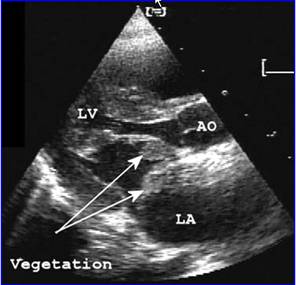

亞急性感染性心內膜炎感染性心內膜炎有一定的好發部位,多發生於血流衝擊或局部產生渦流的部位,如二尖瓣關閉不全的心房面,主動脈瓣關閉不全的心室面,室間隔缺損的右心室面動脈導管未閉的肺動脈內膜面等。

亞急性感染性心內膜炎贅生物所附著的瓣膜有炎性反應及灶性壞死,其周邊有淋巴細胞,纖維細胞及巨細胞浸潤。壞死細胞周圍有新生毛細血管,結締組織及肉芽組織,當炎症消退,贅生物纖維化,表面為內皮細胞所覆蓋,經治療痊癒的病例,三個月才能完全癒合,未治癒的病例,癒合與炎症反應交叉存在。贅生物大而易碎,脫落可致臟器及周圍動脈栓塞,如腎、腦、脾、腸系膜及四肢等,先心病並感染性心內膜炎病例,多並發肺栓塞,局部細菌滋長可使瓣葉產生潰瘍或穿孔,腱索及乳頭肌斷裂及細菌性動脈瘤。抗原-抗體複合物在腎血管球沉積,可發生腎血管球性腎炎,由於免疫反應引起小動脈內膜增生,阻塞及小血管周圍炎,表現為皮膚及黏膜的淤點,發生於手指、足趾末端的掌面,稍高於皮面,有壓痛,5-15mm大小,稱奧氏(Osler)結節,後掌及足趾有數毫米大小的紫紅色斑點,稱為Janeway氏結節。

5、超聲心動圖心瓣膜或心內膜壁有贅生物,及固有心臟病的異常表現。